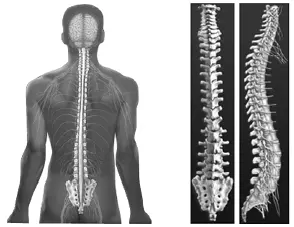

Позвоночник

В анатомии человека позвоночник (позвоночный столб или спинной хребет) – это столб, внутри которого находится спинной мозг. Он состоит из 7 шейных позвонков, 12 грудных позвонков, 5 поясничных позвонков, крестца и копчика. С грудными позвонками связаны ребра грудной клетки.

Позвоночник человека

Спинной мозг – это массив нервной ткани и дополнительных клеток толщиной с человеческий палец. Он тянется из мозга по всей длине позвоночника. Нервы, из которых он состоит, заключены в особый футляр и окружены спинномозговой жидкостью, которая действует как подушка, защищая их от ударов о внутреннюю часть позвоночного столба.

Спинной мозг образует парные нервные отростки на уровне каждого позвонка, за исключением верхнего шейного позвонка. Эти нервные ответвления выходят из позвоночника по обеим сторонам через отверстия между позвонками.